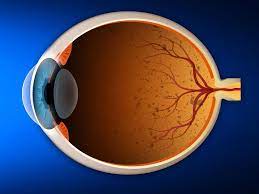

قیمت: 78٬000 تومان - دسته بندی فایل: پاورپوینتپاورپوینت بیماری های شبکیه

فروش ویژه پاورپوینت حرفه ای بیماری های شبکیه با تخفیف استثنایی فقط 68774 هزار تومان تعداد اسلاید: 45 اسلاید